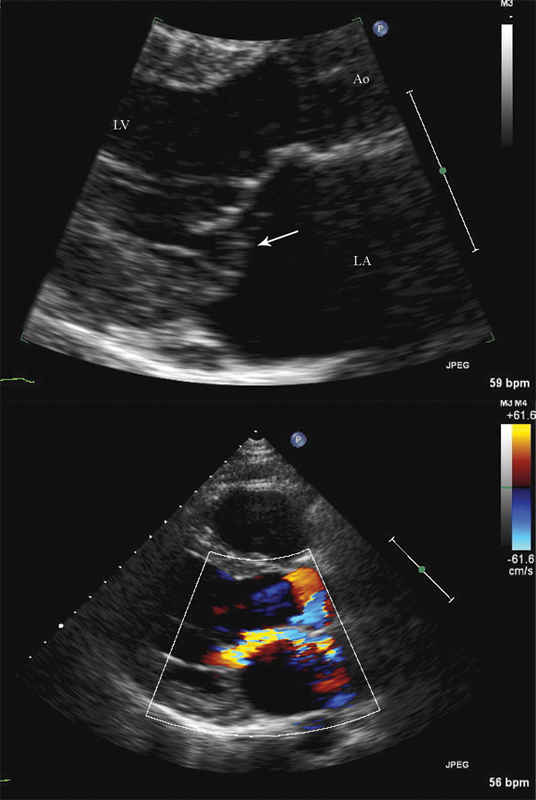

فحوصات تشخيصية لبعض امراض القلب والشرايين التاجية